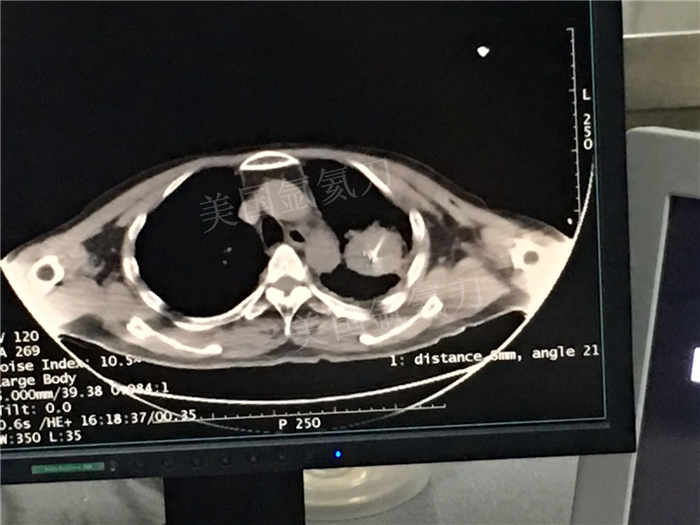

发布人:美国氩氦刀技术官方网站 发布时间:2018/7/5 10:57:23

下一篇:中日友好医院氩氦刀冷冻消融治疗胸膜间皮瘤